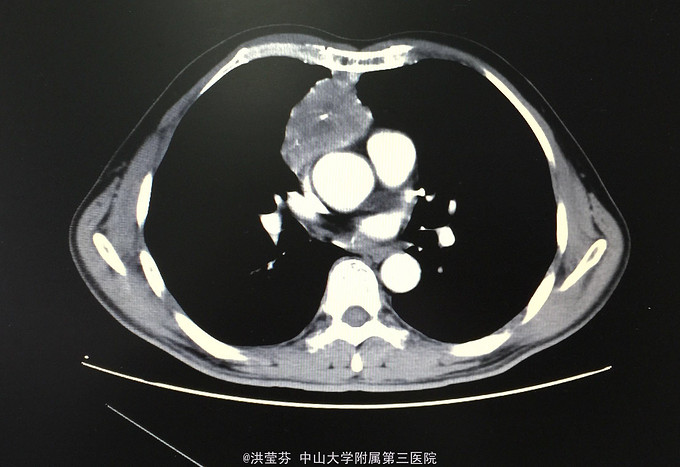

查体:KPS 60分,BSA 1.83m2,T 38.5℃,全身浅表淋巴结未触及明显肿大,胸壁可见浅表静脉曲张,呼吸急促,左下肺、右中下肺呼吸音明显减弱,其余肺野呼吸音促,可闻及少许实性啰音,心率110bpm,律齐,腹软,全腹无压痛、反跳痛,未扪及明显包块,肝脾肋下未触及,移动性浊音(——),肠鸣音正常,4次/分,双下肢无凹陷性水肿。 辅助检查:血常规无特殊,生化转氨酶稍升高,低钠低氯,CRP 227.9mg/L,凝血四项:Fib 8.14g/L。复查胸部CT提示:1.胸腺癌并纵膈淋巴结及双肺多发转移瘤,右心房、上腔静脉受侵并癌栓形成,病变较前进展。2.双肺炎症,以右肺为著。3.双侧胸腔及心包积液。上腹部CT提示:1.下腔静脉早显并肝表面多发侧支形成,考虑右心流出道阻塞所致;腹壁静脉曲张。头颅MR提示右侧颞叶强化灶,结合病史,考虑转移瘤,伴瘤灶少量出血可能,瘤周脑水肿。

入院诊断:1.A型胸腺瘤并纵膈淋巴结、双肺、脑转移,2.上腔静脉血栓形成(癌栓)。入院后予利尿、甲强龙减轻水肿和压迫治疗,“亚胺培南”抗感染治疗后咳嗽、气促症状较前明显缓解,提问逐渐恢复正常,后予CIK免疫细胞回输治疗。